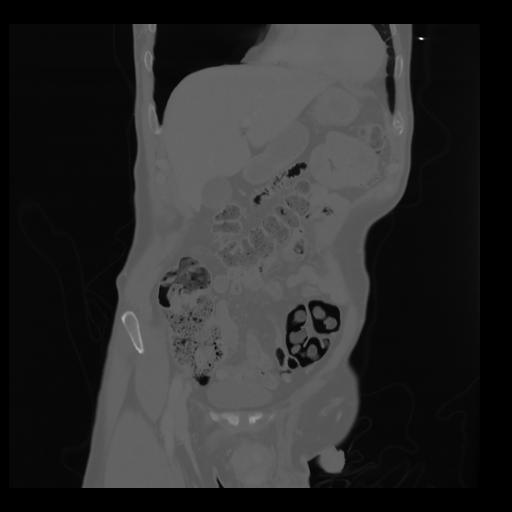

35 CUERPO,CE,Coronal,3.000,CUERPO,Coronal,